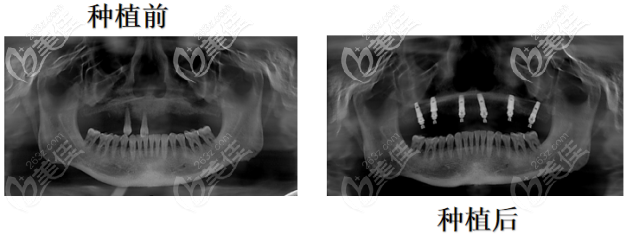

(Ct片下的牙部形态)

(种植前后对比照片)